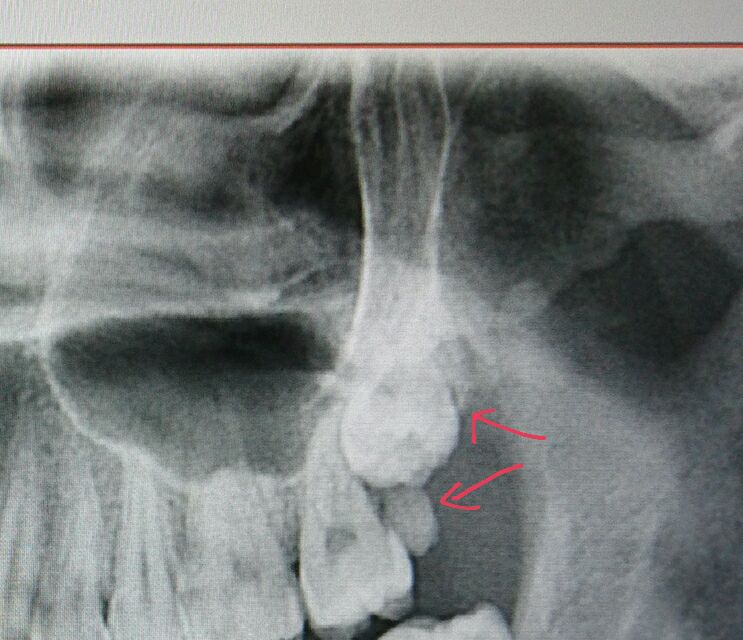

其他三颗位置很正,就这一块地方长了两颗

今天医生说把下面这个干掉,挤在上面的这颗应该能长下来

希望会长下来,都长在脸颊上了,好几年了,太造孽了,难怪脸上不舒服!

上面的那颗,如果直接拔可能会造成口腔和鼻窦穿孔,多找些医生看看。

看着你的牙槽骨也有点不正常。